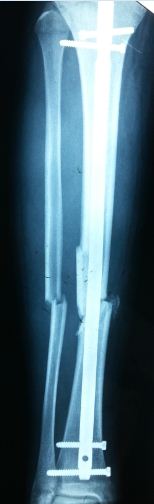

Εξωτερική Οστεοσύνθεση

Η εξωτερική οστεοσύνθεση είναι η χειρουργική τεχνική συγκράτησης ενός κατάγματος σε θέση ανάταξης με τη χρήση ενός συστήματος ράβδων και βελονών. Η εστία του κατάγματος δεν ανοίγεται χειρουργικά και η ανάταξή του επιτυγχάνεται με έμμεσο τρόπο.

Είναι μια χειρουργική τεχνική μικρής παρεμβατικότητας και ενδείκνυται στη σταθεροποίηση καταγμάτων που συνοδεύονται από σοβαρές βλάβες των μαλακών μορίων που τα περιβάλουν. Πέρα από την τραυματογία, η χρήση της εξωτερικής οστεοσύνθεσης επεκτείνεται και στην επανορθωτική χειρουργική αλλά και στην αύξηση μήκους ενός οστού (διατατική οστεογένεση).